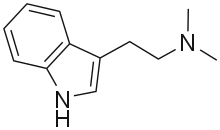

| DMT | Animals, plants | H | CH3 | CH3 | N,N-dimethyltryptamine | 61-50-7 |